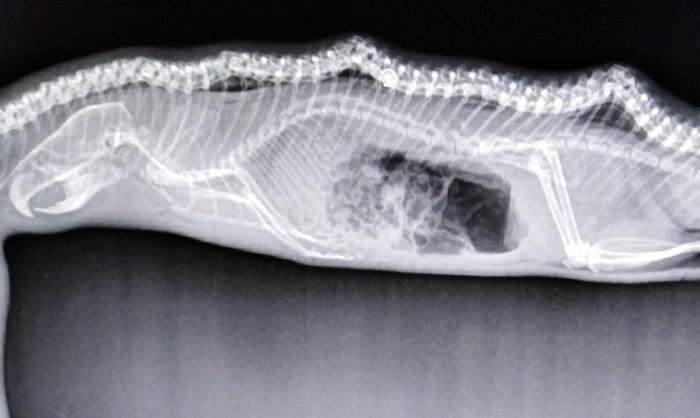

(蜘蛛网eeook.com报道)据ETtoday:澳洲达尔文(Darwin)野生动物保护组织上月29日发现一条大水蟒疑似遭车辆撞击,送医抢救后不治。特别的是, 院方透过X光片清楚拍下它的「最后的晚餐」,推测可能是它吃太饱,导致爬行速度变慢,才会在过马路时出车祸。

负责治疗的副院长Andrea Ruske表示,「有趣的是,这只水蟒吃了一只大老鼠,而且连骨头也变形了。」她猜测,水蟒之所以被撞到,很可能是因为吃太饱,导致行动缓慢,因此在过马路时发生憾事。

许多网友看完感到不可思议,怀疑水蟒可能本身就有严重骨头疾病;组织粉专则回覆,「对,它同时也有代谢性骨病,这在野生蛇类中相当少见,但可以肯定的是它绝不是宠物。」